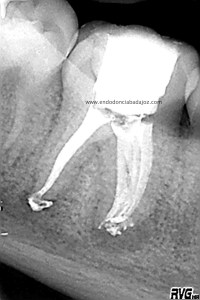

Bueno, pues hoy voy a poner un casito de otro molar inferior, un 4.6, de un chico de unos 14 años. Presentaba una necrosis con una lesión periodontal

Cuando tratamos a niños, tenemos que entender que en muchas ocasiones los conductos no se han cerrado formando sistemas de conductos muy difíciles de limpiar tanto química como mecánicamente. Es este caso, presentaba un istmo mesial acintado que lo tratamos como si tuviese varios conductos. Colocamos H de Ca, soy ,en ciertos casos, un defensor del medicamento intraconductos, con lo que lo hicimos en  dos sesiones.

Se trata de un caso similar a este otro visto desde oclusal, observamos un istmo en la raiz mesial que tratamos como si fuesen varios conductos.

Una vez que hemos limpiado los conductos con un sistema de instrumentación  Protaper en combinación con limas K3. Pasamos a obturar los mismos con una técnica de condensación vertical de ola contínua de Buchanan y un backfilling con la gutapercha inyectada de la pistola ObturaII. Tomamos varias proyecciones, orto-mesio-distal